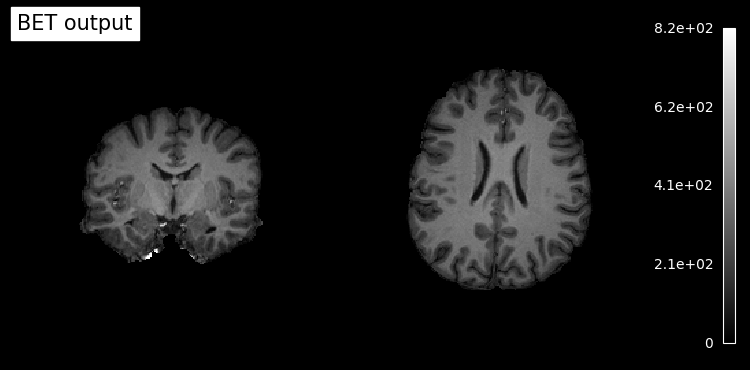

# Plot skullstripped output file (out_file) through the outputs property

plotting.plot_anat(res.outputs.out_file, title='BET output', cut_coords=(10,10,10),

display_mode='ortho', dim=-1, draw_cross=False, annotate=False);